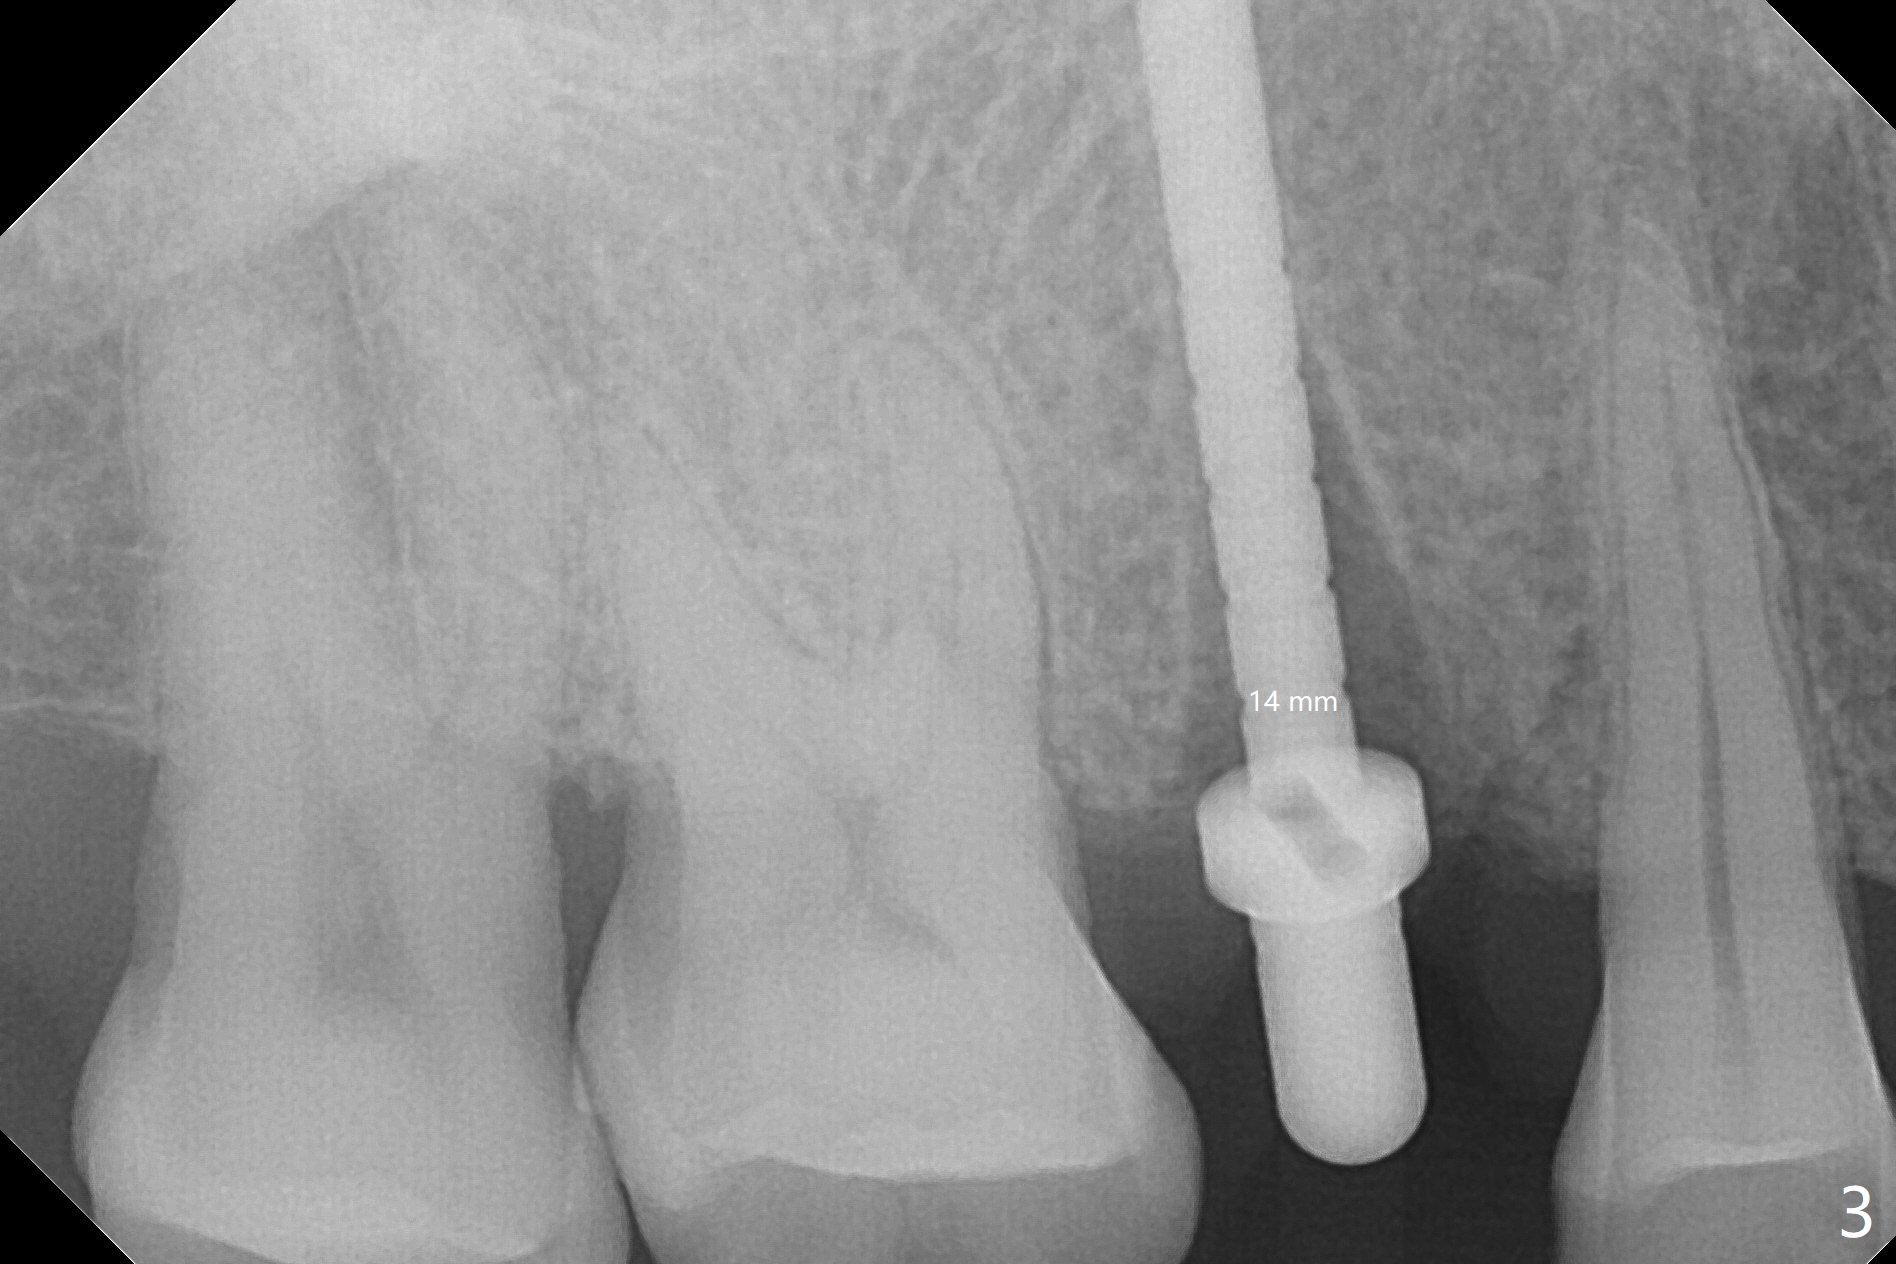

A 61-year-old man cracks the tooth #4 while chewing on a piece of chicken bone (Fig.1,2). Initial osteotomy appears to be able to hold a 16 mm long implant (Fig.3). After sequential osteotomy, a 4x16 mm implant is initially unable to be seated low enough for the buccal crest. Following packing the osteotomy with Vanilla Graft (.5-1 mm) and additional 2-3 mm depth of osteotomy, the implant is placed slightly apical to the buccal crest (Fig.4,5); with placement of Vanilla Graft (*) and a 4.5x4(4) mm abutment, an immediate provisional is fabricated to close the socket. The provisional is removed 3 months postop because of poor local oral hygiene (Fig.6,7). The gingiva is healthy 2-3 weeks later; it is easy to take impression (Fig.8).